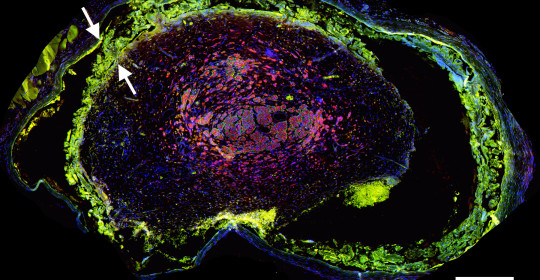

Figures A-D: Immunostained regenerating tissues after 6 weeks; (a and b) mid-conduit sections were stained for GLUT1 (green)/S100 (red)/DAPI (blue) in (a) NoMgSa and (b) MgSa animals (*cavity left by Mg, arrows delineate conduit material, bar=300μm). (c and d) Regenerating nerve mini-fascicles, indicated by arrows, run close to the Mg cavities, which are marked by * and arrowheads. The same staining was done on the section in (c), while the section in (d) was stained with ED1 (green)/NF200 (red)/DAPI (blue). Note GLUT1þ perineurium in (c) and thin layer of ED1+ macrophages above arrowheads in (d) (bar in c and d=50μm).

NoMgSa: saline filler only; MgSa: saline and Mg; GLUT1: glucose transporter 1; DAPI: 4’ 6-diamidino-2-phenylindole.2